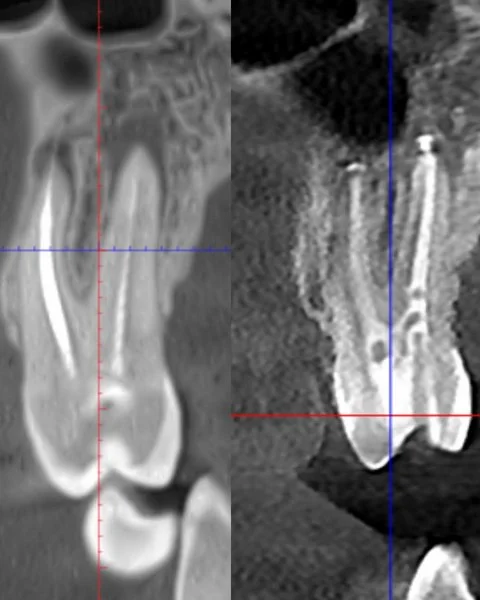

Tak widzimy ząb bez mikroskopu

Widok zęba pod mikroskopem